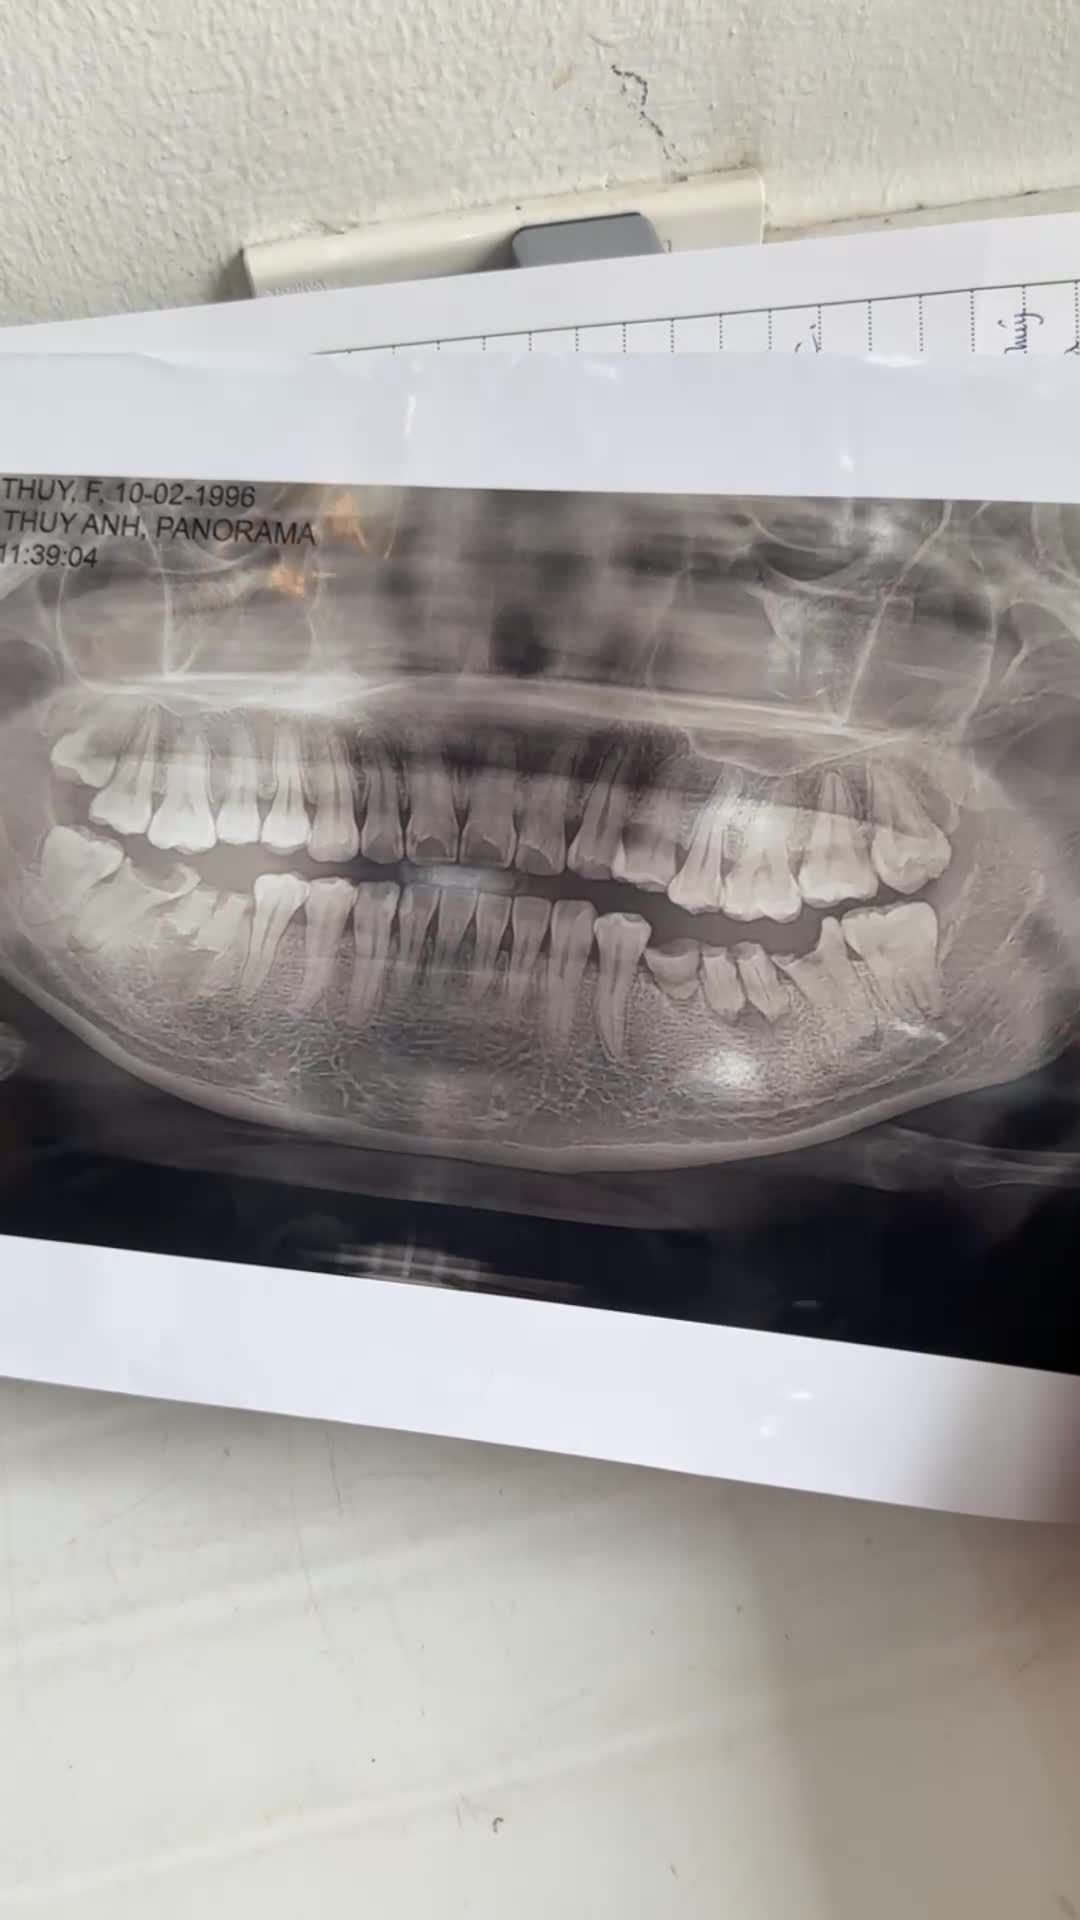

Ca nhổ răng khôn số 48 mọc kẹt, gây dắt thức ăn và khó chịu cho khách hàng và các chân răng sâu hỏng.